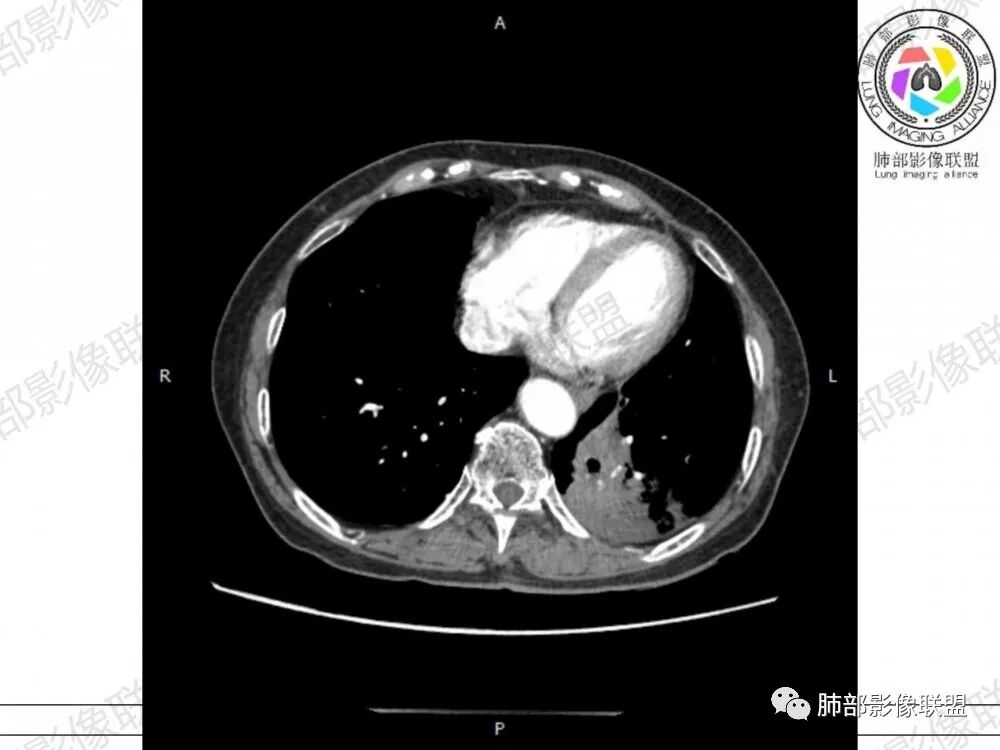

胸CT:左下叶胸膜下大片斑片影,长轴沿胸膜分布,实变、GGO混杂,磨玻璃边界清晰,粘液密度,小叶内间隔增厚,支气管进入后堵塞(枯枝),增强轻中度强化,血管造影征。常规考虑:肺腺癌?淋巴瘤?鉴别不典型病原体感染。

2、影像表现:无肺气肿背景,病变定位于左肺下叶背内侧基底段,病灶呈不规则团块影,靠近胸膜侧,其内密度不均匀,内见空洞、实变及磨玻璃影,磨玻璃影呈碎石路征,边界清楚,实性肿块边界膨隆,其内见空洞。空洞周围比较实。病灶较大的支气管通畅,细小的支气管成“枯枝征”。无胸膜增厚及胸膜腔积液,增强扫描呈中度强化,见血管造影征。

2、典型的粘液腺癌,收缩力很弱,肺泡壁断裂常有,张力存在,早期较少出现张力表现,破坏力偏弱,支气管与肺血管大多保留,所以增强病灶内见强化血管影(血池),也是粘液腺癌另一个特点。

2、肺淋巴瘤:CT表现:两肺多发实变,多伴有空气支气管征,空泡征、磨玻璃密度、肺叶局部实变、小叶间隔增厚、气管壁增厚、增强见血管造影征,与本病有重叠,由于粘液腺癌有重力作用、粘液腺癌易发生于下肺胸膜下有助于鉴别。